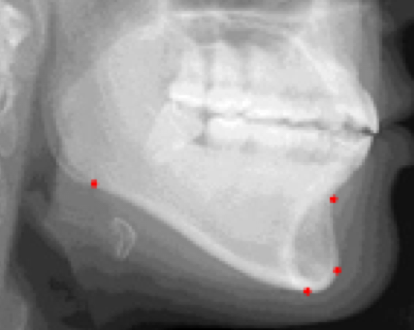

Q

Point B - inntermost point on contour of md between incisors and bony chin

Pogonion (Pog) - most anterior part on contour of chin

Menton (Me) - most inferior point of md symphysis

Gonion (Go) midpoint of contour connecting ramus and body of md